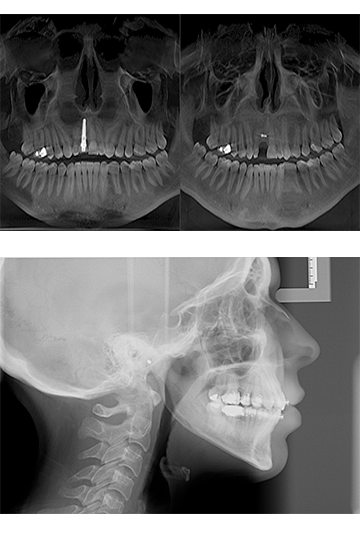

Siempre a la vanguardia, el Laboratorio de Radiología Diagnóstica en Ortodoncia S.A. de C.V. tiene para todos los cirujanos que deseen contar con tecnología de punta el servicio de Radiología Digital más avanzado de México y el Mundo, que ya no requiere de escaneo, proceso selectivo, revelado, ni productos químicos, además ofrece mínimos niveles de radiación.

La radiología digital, cuya transmisión de imágenes a través de un sensor a la computadora desde el equipo de rayos X, permite administrar, visualizar, analizar imágenes radiológicas en una variedad de 256 tonos de gris.

La radiología computarizada permite obtener calidad, cantidad y variabilidad de datos porque cuenta con un sinnúmero de herramientas de análisis con las que usted puede explorar hasta elúltimo detalle para llegar a un diagnóstico preciso.

Todo esto nos permite afirmar que la radiología digital tiene un potencial irrefutable que hace posible que de una sóla imagen se pueda obtener información a detalle.

En 2003, el laboratorio de radiología diagnóstica en ortodoncia S.A. de C.V., pone a disposición de odontólogos y ortodoncistas el primer Orhtopanthomógrafo Digital, siendo los primeros en México en ofrecer tecnología de punta para sus consultorios y pacientes. Dicha innovación le permite a los especialistas contar con un sinnúmero de herramientas de diagnóstico y análisis.